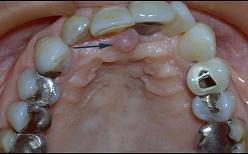

问题 切牙乳突是排列上中切牙的解剖标志、是因为 ( )

选项 A.切牙乳突的位置变化较小 B.切牙乳突位于上颌腭中缝的前端 C.切牙乳突下方为切牙孔、排牙时要防止此处压迫 D.切牙乳突与上颌中切牙之间有较稳定的关系 E.两个上中切牙的交界线应以切牙乳实为准

答案 D